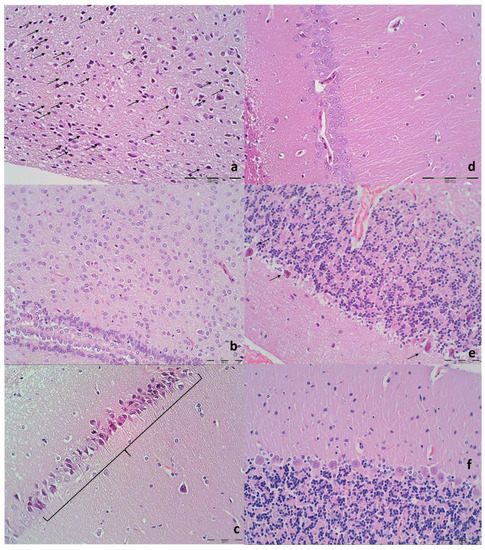

3.9. Histology

| Brain Area | Grading | Percent Area Affected | Morphological Changes |

| Cerebral and cerebellar cortex, hypothalamus, thalamus, hippocampus | 1 | ≤10 | Small, patchy, complete or incomplete infarcts |

| 2 | 20–30 | Partly confluent complete or incomplete infarcts | |

| 3 | 40–60 | Large confluent compete infarcts | |

| 4 | >75 | In cortex; total disintegration of the tissue, in hypothalamus, thalamus, hippocampus; large complete infarcts | |

| Cerebral and cerebellar cortex, hypothalamus, thalamus, hippocampus | 1 | ≤20 | A few karyopyknotic of neuronal cells |

| 2 | 50 | Patchy areas of karyopyknotic areas | |

| 3 | 75 | More extensive of karyopyknotic areas | |

| 4 | 100 | Complete infarction |